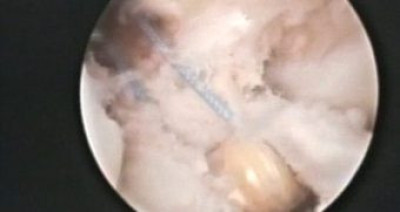

Finalizando atornillado de injerto a nivel femoral